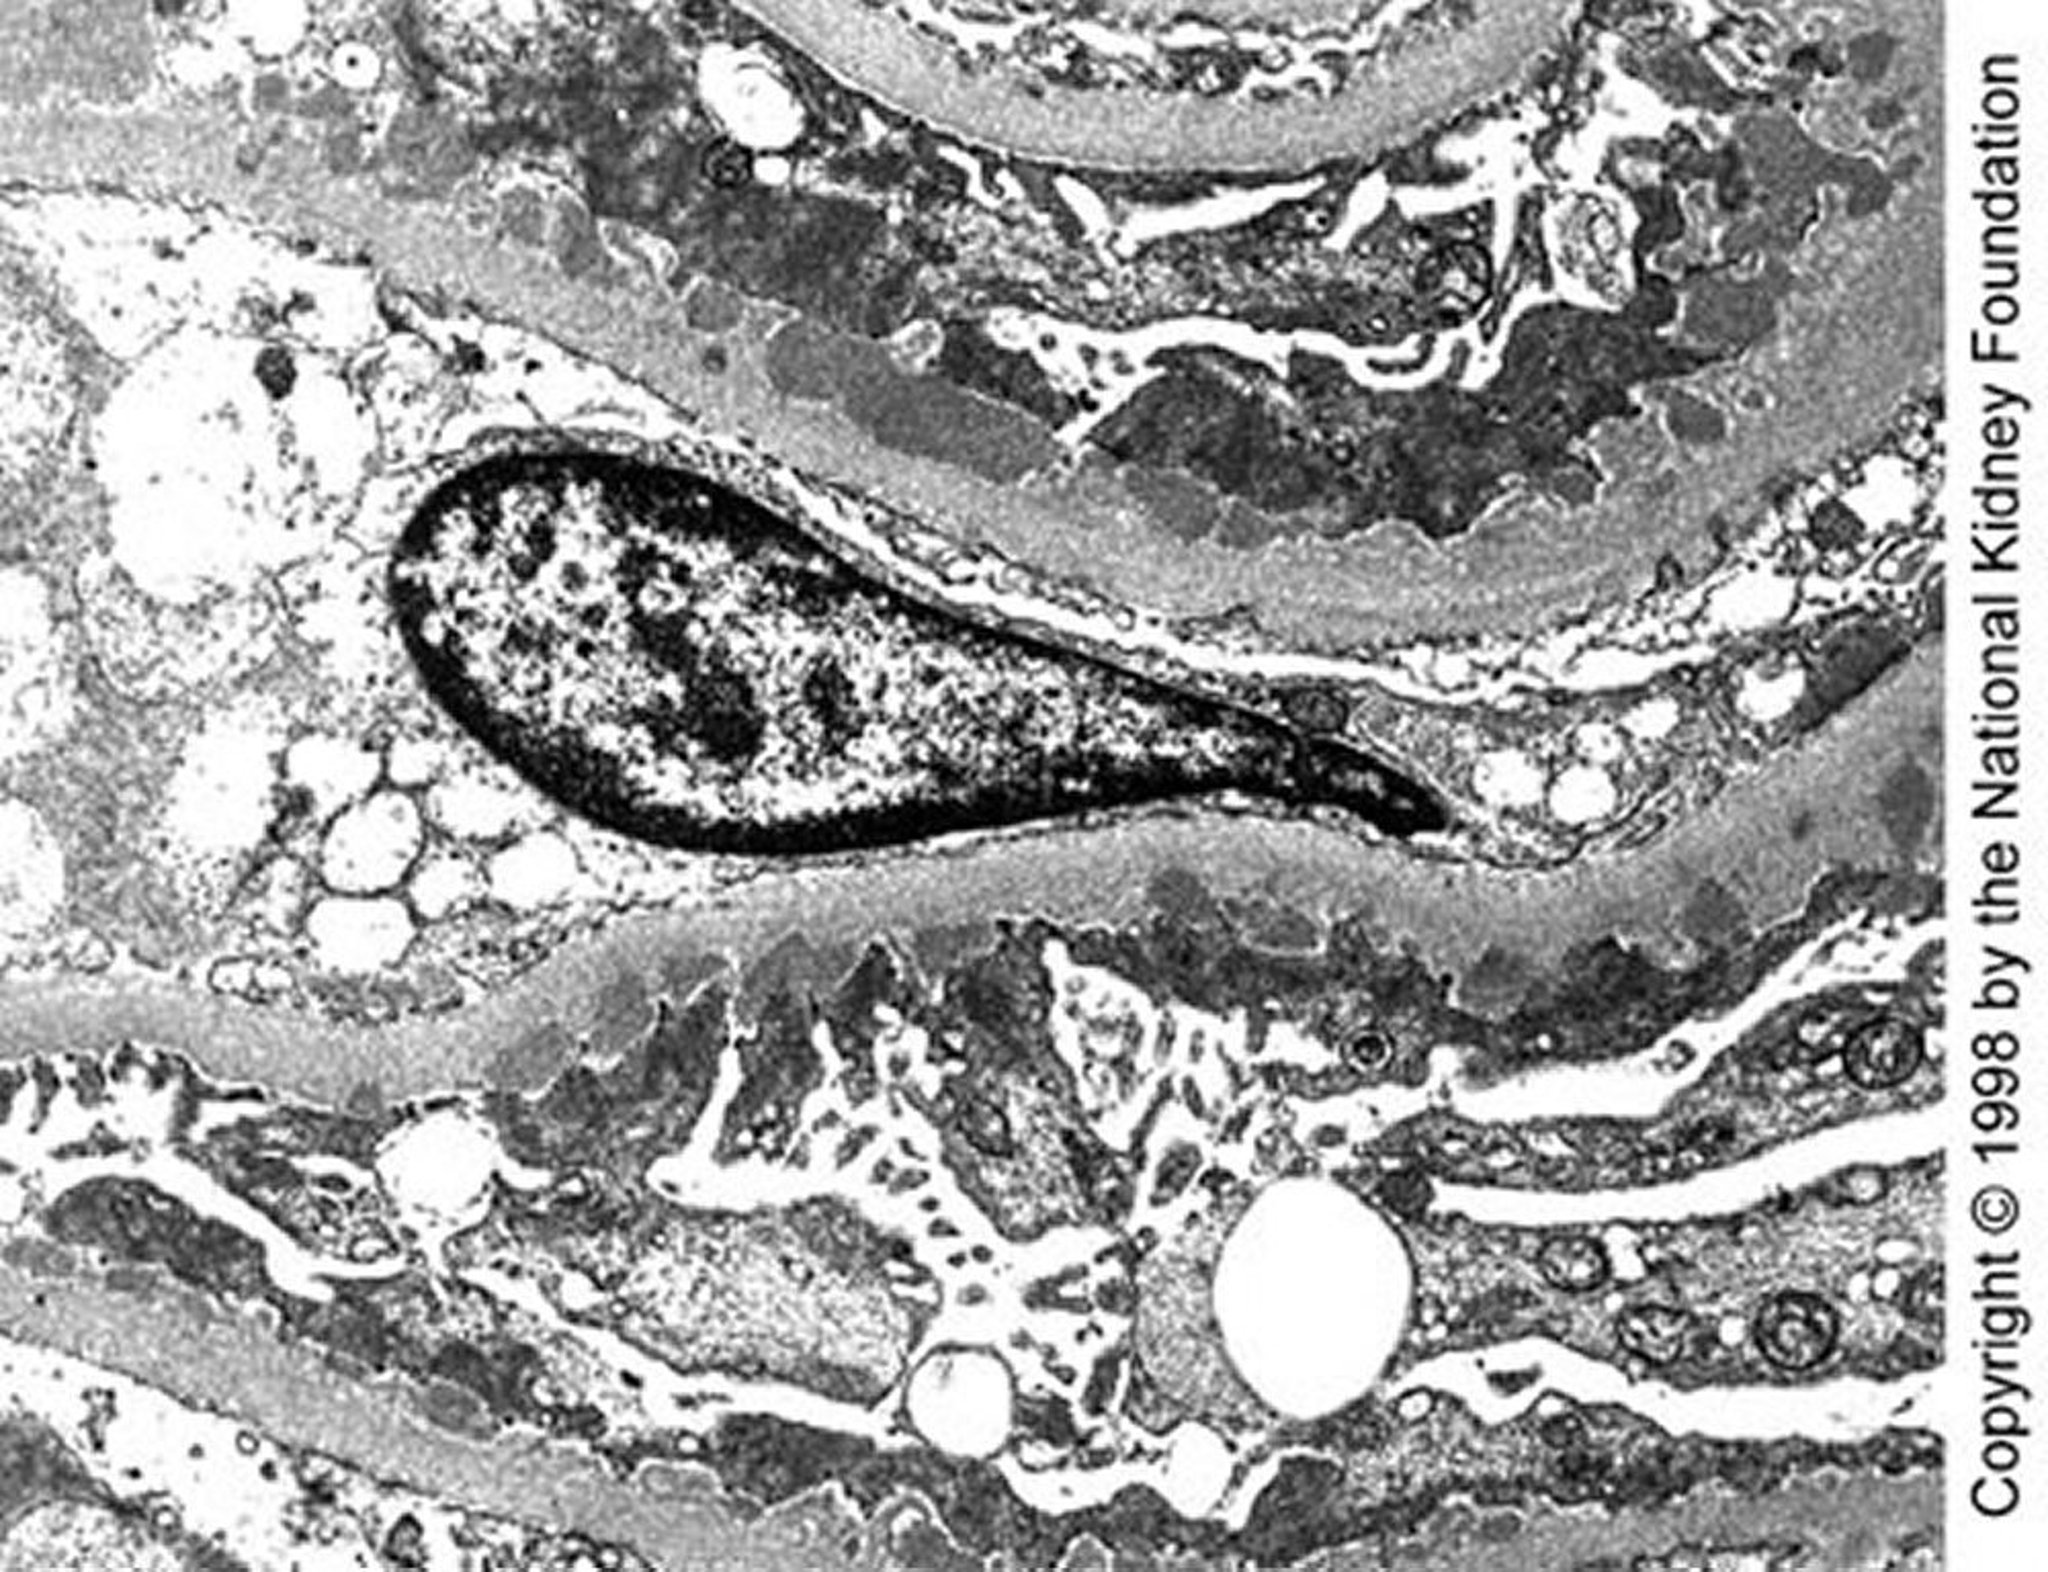

Nefropatia membranosa (depósitos densos)

Observam-se depósitos densos subepiteliais de tamanho médio por microscopia eletrônica na doença de fase I tardia (× 10.200).

Image provided by Agnes Fogo, MD, and the American Journal of Kidney Diseases' Atlas of Renal Pathology (see www.ajkd.org).